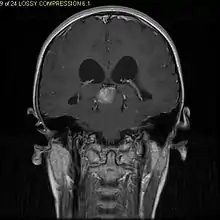

Usually – depending on the interview of the patient and after a clinical exam which includes a neurological exam and an ophthalmological exam – a CT scan and/or an MRI scan will be performed to confirm the presence of a tumor. They are usually easily distinguishable from normal brain structures using these imaging techniques. A special dye may be injected into a vein before these scans to provide contrast and make tumors easier to identify. Pilocytic astrocytomas are typically clearly visible on such scans, but it is often difficult to say based on imaging alone what type of tumor is present.